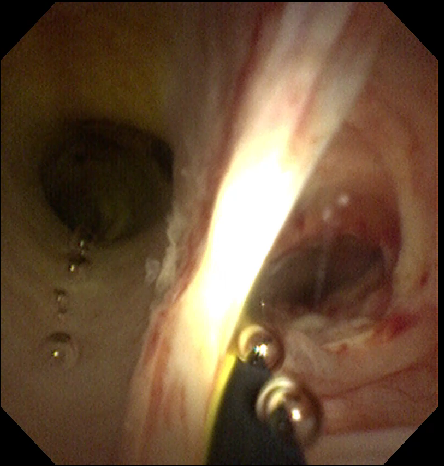

我院李虎城主任医师接诊阅片后,综合评估老人的病情,最终决定为老人行内镜下胆囊胆管取石术+胆囊引流管置入术术中见胆总管扩张,胆囊及肝内胆管正常显影,见胆总管粘膜基本正常,可见多发小碎石,沿导丝经胆囊管进入胆囊,胆囊内见大量泥沙样小颗粒结石、胆汁黏稠,胆囊壁未见明确新生物大量生理盐水冲洗胆囊,见墨绿色泥沙样胆汁流出。退出胆道子镜,取石球囊取出胆总管内结石。手术过程顺利,术中生命体征平稳,术后安返病房。术中字母镜图像如下